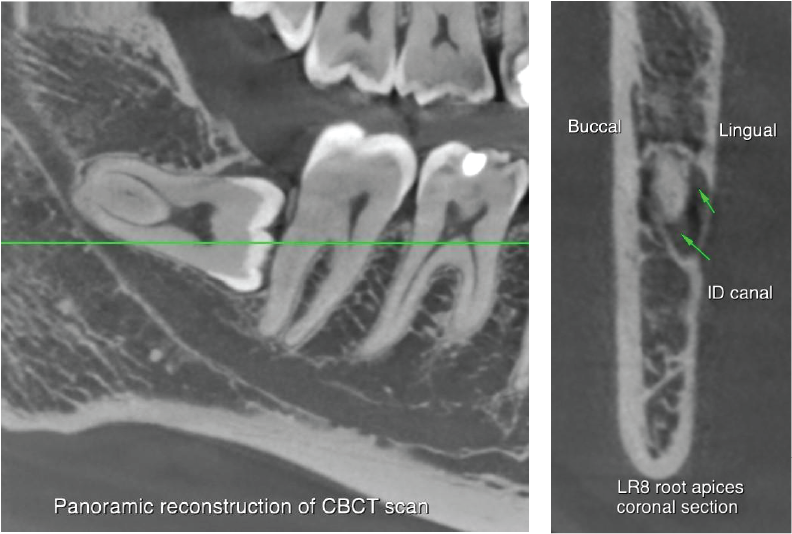

CBCT scan of LR678 taken. There appears to be occlusal caries in the UR7 and possibly the LR7. LR67 have no periapical radiolucencies.

The LR8 is horizontally impacted, with two roots which appear to be fused. The inferior dental canal is narrowed and has a tight contact with the lingual surface of the apical half of the LR8 roots and then runs below the LR8 tooth. The canal is approximately 2.5mm below the mesial cemento-enamel junction of LR8. The findings indicate an intimate relationship between the canal and LR8.